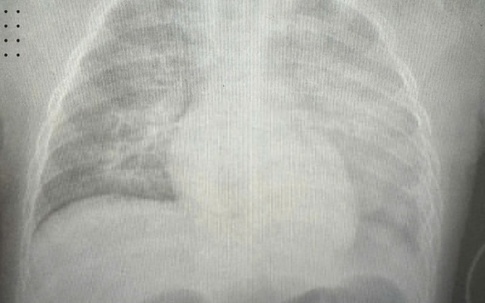

Bé 7 tháng tuổi ở Quảng Ninh suy hô hấp do bệnh sởi biến chứng nặng

Mẹ và béGĐXH - Bệnh nhi 7 tháng tuổi mắc bệnh sởi biến chứng viêm phổi nặng, suy hô hấp kèm tiêu chảy cấp. Được biết, bệnh nhi chưa đến độ tuổi tiêm phòng và có tiền sử viêm phổi hai lần trong những tháng đầu đời.

Sống khỏeGĐXH – Trẻ được đưa đến viện trong tình trạng ban sởi toàn thân, phù nề mi mắt, xuất huyết tại các vị trí tiêm truyền. Chẩn đoán hội chứng suy hô hấp cấp tiến triển (ARDS), một biến chứng nặng của sởi.

Sống khỏeGĐXH – Tại Bệnh viện Nhi Hà Nội, khoảng 30% các bệnh nhi nhập viện trong tình trạng nặng, tổn thương phổi, phải can thiệp thở oxy hoặc thở máy.

Y tếGĐXH – Tại bệnh viện, bệnh nhân được chẩn đoán mắc sởi có biến chứng viêm phổi, được điều trị tích cực để thoát cơn nguy kịch.